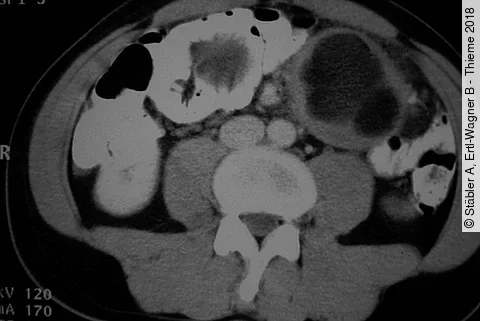

Rezidivierende ödematöse Veränderungen im Gastrointestinaltrakt, die zu einer Obstruktion und zum (Sub)Ileus mit rezidivierendem Erbrechen/Reflux oder Stuhlverhalt führen. Welche Ursachen sind möglich?

Rezidivierende ödematöse Veränderungen im Gastrointestinaltrakt, die zu einer Obstruktion und zum (Sub)Ileus mit rezidivierendem Erbrechen/Reflux oder Stuhlverhalt führen. Diese Ursachen sind möglich.